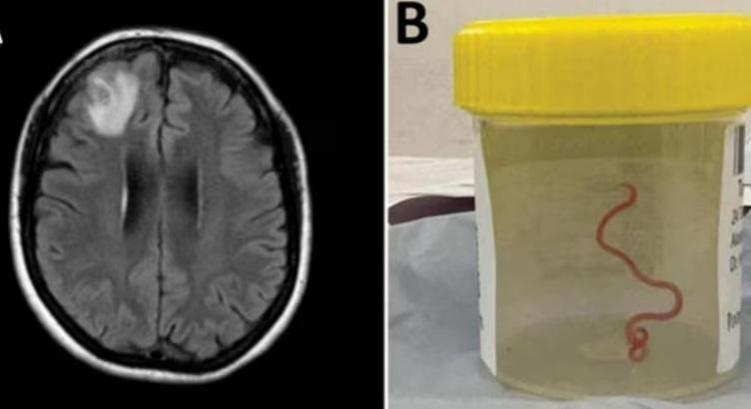

In a world's first such case, a team of Australian neurosurgeons has removed an eight cm-long parasitic roundworm from a patient who complained of forgetfulness and depression.

The Ophidascaris robertsi roundworm was pulled from the patient after brain surgery -- still alive and wriggling. It is suspected larvae, or juveniles, were also present in other organs in the woman's body, including the lungs and liver.

"This is the first-ever human case of Ophidascaris to be described in the world," said Sanjaya Senanayake, leading ANU and Canberra Hospital infectious disease expert in a paper published in the journal Emerging infectious diseases.

"To our knowledge, this is also the first case to involve the brain of any mammalian species, human or otherwise. Normally the larvae from the roundworm are found in small mammals and marsupials, which are eaten by the python, allowing the life cycle to complete itself in the snake," Senanayake added.